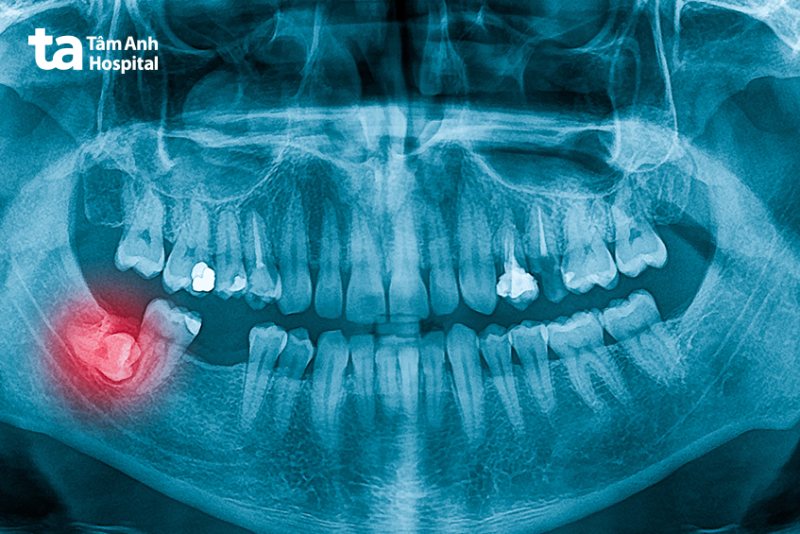

Đối với các trường hợp răng khôn mọc ngầm, mọc lệch hoặc chen lấn vào các răng xung quanh gây viêm nhiễm, bác sĩ sẽ chỉ định thực hiện nhổ răng khôn.